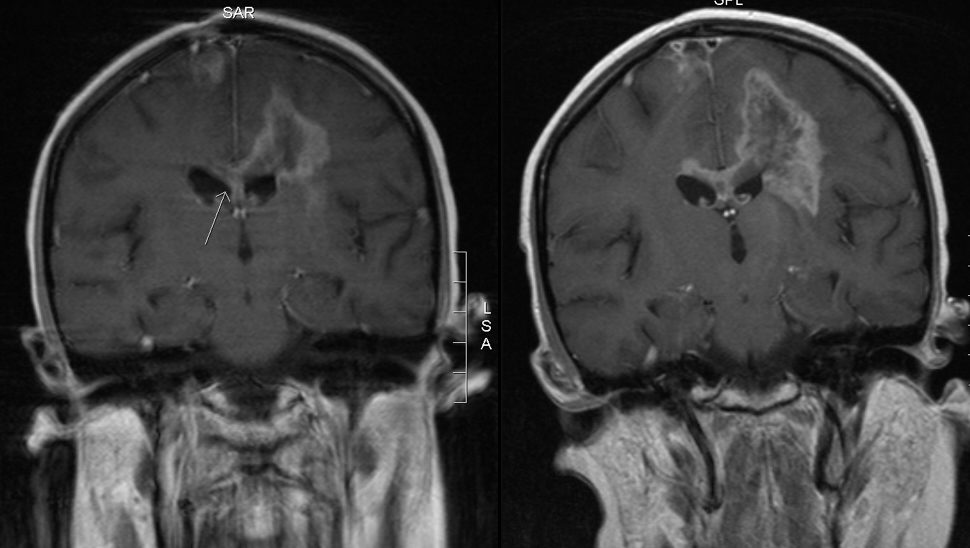

These images show that the rest of the tumor hadn’t seemed to notice there’d been treatment going on:

Back view MRI before and after treatment

(l) 27 Oct 2006: a month after her first MRI, before the biopsy, 3 weeks before treatment began

(r) 27 Feb 2007: 1.5 months after the end of radiation and vincristine-cisplatin. The dark center in the tumor is necrosis (dead tissue), which could be from radiation; it’s also a hallmark of glioblastoma multiforme (GBM): a GBM grows so quickly its blood supply can’t keep up with it, and the center dies off.